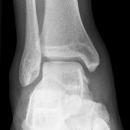

Sprunggelenk

Weber A

Es wurden keine Bilder gefunden.

Weber B

Weber C + dorsales Volkmann

Trimalleoläre

Vorderes Volkmann + lat. Talusschulter